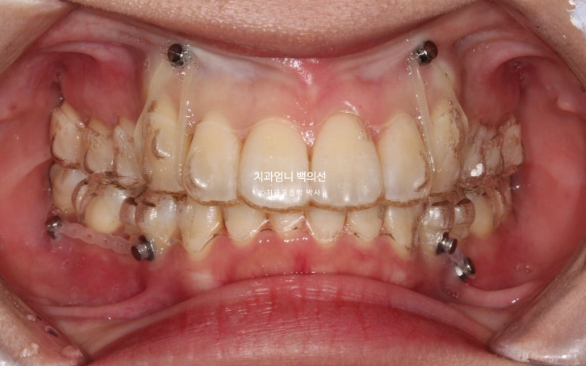

23.11

치료시작 8개월차 발치공간으로 앞니가 이동하면서 원래 깊었던 앞니 교합이 점점 더 깊어지는 것이 관찰됩니다.

이 부분 해결을 위해서는 원래 계획에 없었지만 앞니에 미니스크류 2개를 추가로 식립하고 고무줄을 걸기 시작합니다.

중간중간 장치를 잘 못 낀 기간이 있어서 장치가 잘 맞지 않아 예전장치로 돌아가 낀 적도 있습니다.

또 어태치먼트도 장치랑 잘 맞지 않아 어태치먼트도 다시 붙이기도 했습니다

재제작은 할 때마다 새 장치를 기다리는 시간이 한 달 이상입니다.

그 시간이 아까우니 가능한 최소화 하는 것이 좋습니다.

인비절라인이 잘 안 맞을때마다 재제작을 하면 교정기간이 너무 길어집니다.

23년 3월부터 24년 5월까지 1년 2개월간 52개의 장치를 낀 후 재제작 당시의 모습 보여드리겠습니다.

과개교합은 잘 개선이 되었습니다.

미니스크류와 고무줄의 조합은 인비절라인 발치교정이 성공으로 가는 노하우 입니다.

처음부터 계획하지는 않지만 적절하게 중간에 개입하여 부적절한 치아이동을 컨트롤 하는 중요한 도구입니다.

발치공간이 아직 남아있고 앞니 각도의 개선이 더 필요합니다.

아래 어금니들은 사랑니 공간으로 잘 이동했습니다.